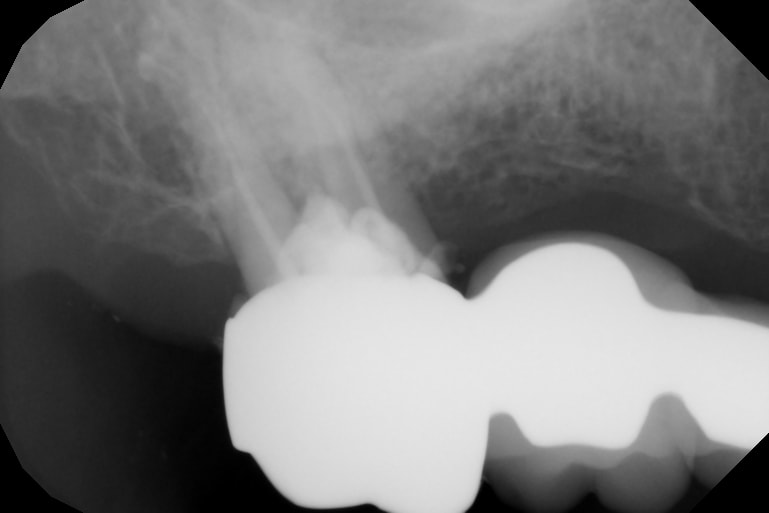

Le problème ici est la tenue de ton pilier postérieur terminal 17 car entre la perforation plancher, la cavité d’accès,

Eh ben y a plus trop de matériau dentaire pour bien tenir l’ensemble.

Je vois bien l’ensemble se désolidariser par l’arrière ou bien casser car fragile.

J'ai aussi la même appréhension que JF35. Pourquoi attendre et espérer que rien ne se passe ?

La cavité d'accès à travers ton bridge ne sera jamais refermée de manière étanche.

Tu as fragilisé ton pilier à l'aveugle, et celui-ci nécessiterait une RMIPP ou un Inlay-Core pour assurer son rôle à présent.

Puis clairement l'endo est insuffisante et il faut mieux la reprendre maintenant avant qu'un LIPOE ne s'installe.

Le pilier n'est pas autantbfragilisé que ne pourrait laisser penser la rx

Un tenon ou un IC compliqué à mettre en oeuvre à travers la couronne

A ta décharge, si j'ose, la dent etait deja limite ou meme deja en furcation., C'etait sportif de conserver cette 17....

difficile d'evaluer avec les 2 radios donnees et ces 2 incidences totalement differentes